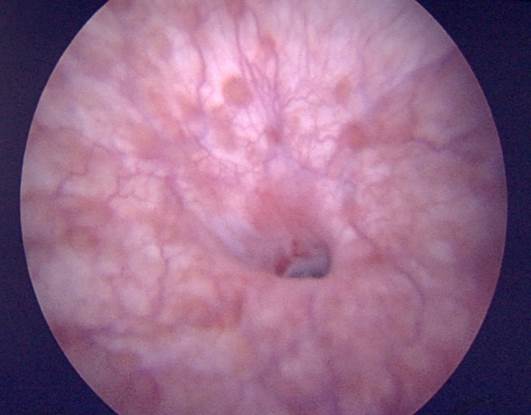

- La cistoscopía es el gold standard para definir la presencia/ausencia de una E/E y la localización del cabo distal de ésta. Aunque se estableció para determinar recurrencias postquirúrgicas, la E/E se confirma con la imposibilidad del paso de un cistoscopio 16-17 Fr.19 Siempre debe realizarse para evaluar además patologías concomitantes como tumores, cálculos, tejidos con pelo (colgajos), extensión de metaplasia escamosa; y el calibre uretral. Sin embargo, en la mayoría de los casos no permite definir la longitud de la E/E y, por lo tanto, hay información faltante para planificar un tratamiento.14,15 (Fig. 4).

| Figura 4. Hallazgos en la cistoscopía. a) Estrechez unión penoescrotal con varios anillos. b) Estrechez bulbar media con moderada fibrosis. c) Estrechez unión bulbomembranosa con fibrosis severa y cambios post-radioterapia. d) Metaplasia escamosa y estrechez de uretra pneana. e) Hallazgo de tumor uretral durante estudio de posible estrechez uretral. |